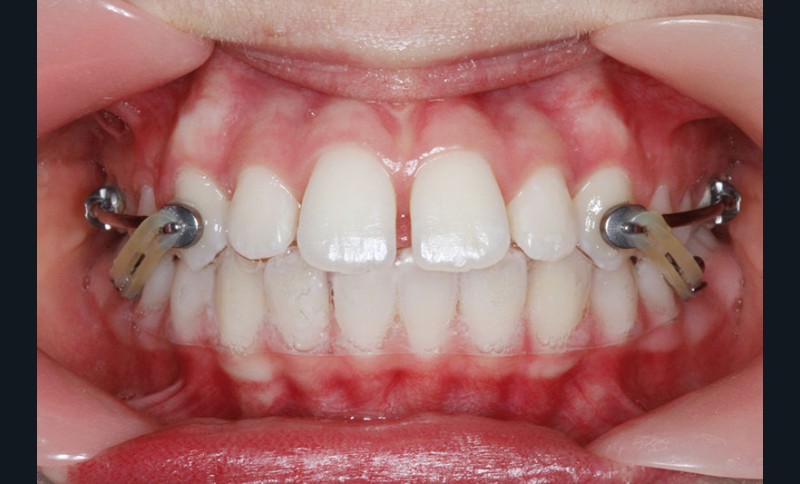

Elle présente une classe II squelettique par rétrognathie mandibulaire et une classe II dentaire molaire et canine droite et gauche associée à une biproalvéolie incisive maxillaire et mandibulaire.

Le pronostic de correction de la classe II est favorable mais il est très important de souligner la vestibuloversion incisive mandibulaire et le risque parodontal associé (fig. 1 à 3).

Il a été décidé de mettre en place un système de correction de la classe II “Motion Classe II Carriere” composé de bras latéraux reliant canine et molaire et d’élastiques de classe II ancrés sur des tubes molaires sur 36 et 46 et une gouttière thermoformée portée en permanence. sAprès dérotation des 16 et 26, recul des secteurs latéraux et libération de la croissance mandibulaire nous mettrons en place un système multiattache autoligaturant passif Carriere SLX 022×028 avec la séquence d’arcs suivante :

1re phase : le Motion Appliance Carriere

Afin d’obtenir la correction de la classe II, nous avons fait porter pendant 3 mois une mécanique d’élastiques intermaxillaires, jour et nuit, avec la séquence suivante (fig. 4):